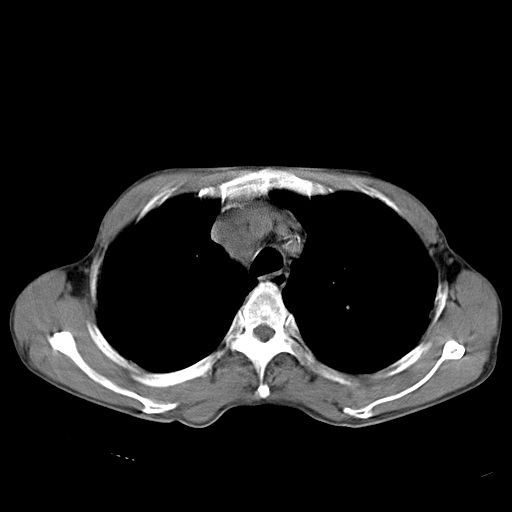

以下是引用苯小孩在2007-5-24 12:47:00的发言:[br]右侧肺门处不均匀密度软组织块影,远端肺组织见斑片模糊影,纵隔内淋巴结明显肿大,边界不清.<纵隔窗第12层面支气管内似见软组织结节>[br]考虑:1、右侧中央性肺癌并阻塞性肺炎并纵隔淋巴结转移可能性大.建议强化或纤支镜进一步检查.[br]2、隆突下淋巴结肿大/食道病变?请做鉴别检查.

以下是引用zhangzhongshou在2007-5-24 12:55:00的发言:[br]1、右肺中叶中心型肺癌并右肺门、隆突下、纵隔淋巴结转移。右肺中叶阻塞性肺炎。

以下是引用jw-830在2007-5-24 15:24:00的发言:[br][br] [br] 考虑右肺中央型肺癌并阻塞性炎症,右肺门及纵隔淋巴结转移。 [br] [br][br]